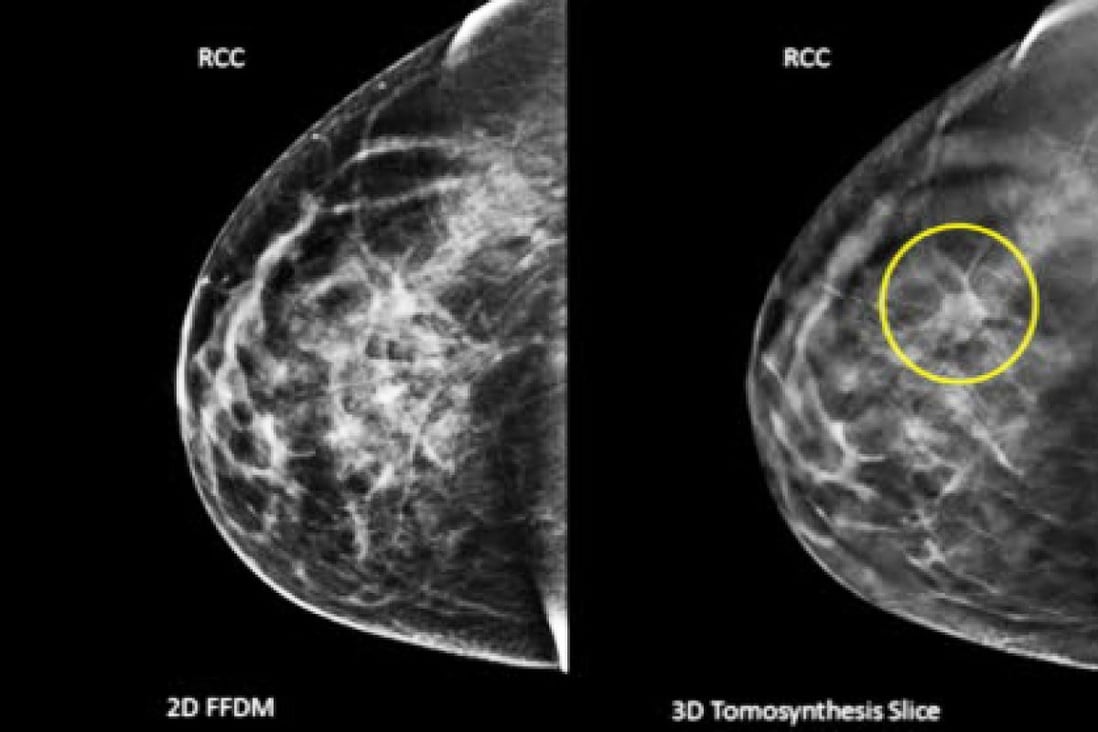

Results showed that breast cancer had the highest survival rate, at 73 per cent. Cancers of the stomach and oesophagus, among the most common, had survival rates of just 27.4 per cent and 20.9 per cent respectively.